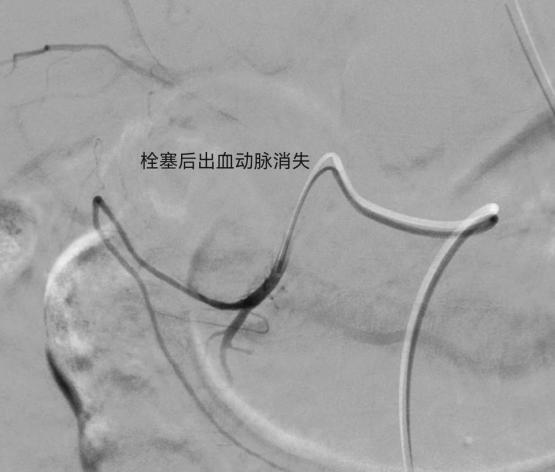

术中造影发现胃十二指肠一分支动脉渗血,随后应用栓塞剂进行栓塞,造影复查出血动脉未见显示,止血成功。术后患者症状改善,未再出现呕血、血色素上升,生命体征平稳。